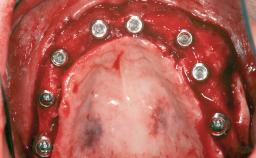

A woman in her mid-fifties was referred by a dental student for dental implant placement. Both posterior segments of the mandible had been edentulous for more than 4 years, the only residual tooth being the right lower first premolar. The patient had used a removable partial denture but was not entirely satisfied with its function. The clinical examination revealed a sharp edentulous ridge in both posterior segments of the mandible, and the patient was told that it would not be possible to insert implants into this thin edentulous ridge without significant augmentation of the alveolar ridge. Her medical history revealed no significant findings and no underlying disease that might have complicated surgical procedures. During the presurgical examination, the patient reported that she was a little apprehensive about bone grafting. After being informed about the surgical procedures and potential postoperative complications, she accepted the proposed surgical plan of bone grafting and subsequent placement of implants.